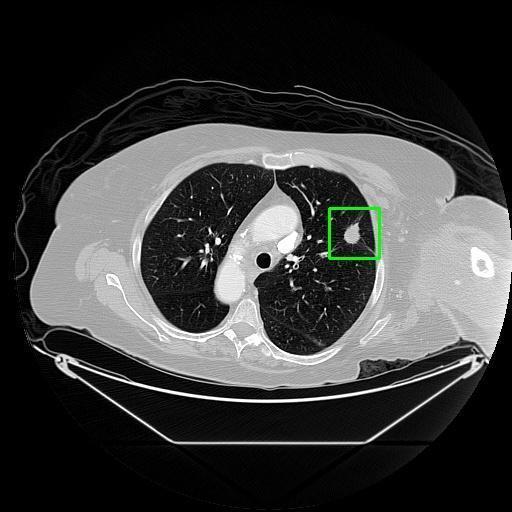

We developed an AI-based system using deep learning models for analyzing lung CT scans to detect and classify pulmonary nodules. We chose the YOLOv11 architecture for its enhanced object detection capability and adapted it specifically for medical imaging, incorporating pixel-level precision and severity classification.

Classification into three severity levels with colored bounding boxes.

Designed a severity classification system that categorizes nodules into null, moderate, and severe using colored bounding boxes, assisting in rapid clinical decision-making.